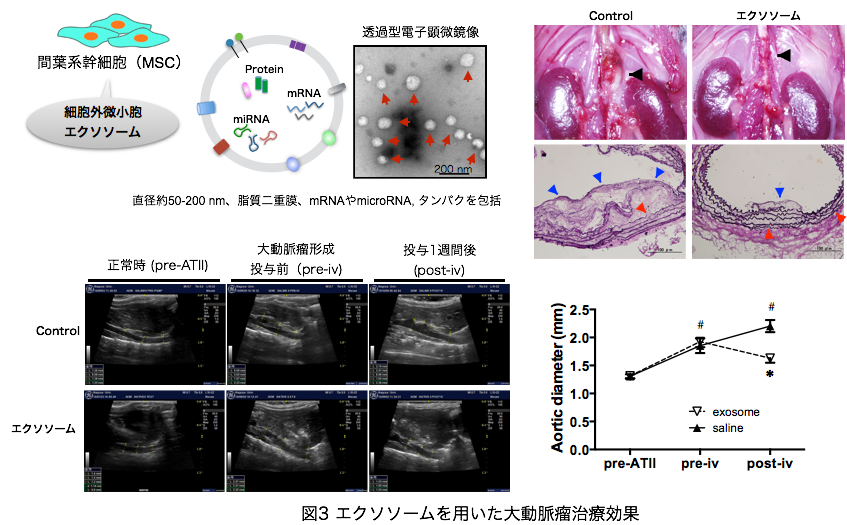

iii) エクソソームを用いた大動脈瘤治療

エクソソームとはほとんどすべての細胞が分泌する微細顆粒である。様々な蛋白、脂質、RNAを含み、様々な生理活性作用を有している。その生理活性作用は由来細胞に依存することがいわれている。そのエクソソームを間葉系幹細胞から単離し、大動脈瘤治療を行うと、治療効果を発現することを我々は世界で初めて発見した。